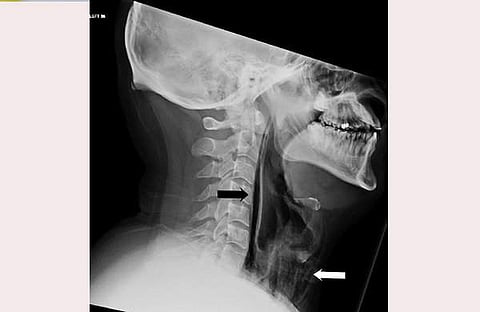

ഭക്ഷണം കഴിക്കുമ്പോള് വേദന അനുഭവപ്പെടുക, ശബ്ദത്തില് മാറ്റം, കഴുത്തില് നീര് തുടങ്ങിയ ലക്ഷണങ്ങള് കണ്ടതിനെ തുടര്ന്ന് യുവാവ് ചികിത്സ തേടിയതോടെയാണ് തൊണ്ട പൊട്ടിയ കാര്യം കണ്ടെത്തിയത്. തുമ്മല് അടക്കിപ്പിടിക്കാന് ശ്രമിക്കുന്നതിനിടെ, തൊണ്ടയിലെ ചില കോശങ്ങളില് വായു കുടുങ്ങിയതിനെ തുടര്ന്നാണ് തൊണ്ട പൊട്ടിയതെന്ന് ഡോക്ടര്മാര് പറഞ്ഞു. ശ്വാസനാളത്തിന്റെ സ്വമേധയാ ഉള്ള വിള്ളല് വളരെ അപൂര്വമാണ്. സാധാരണയായി ഛര്ദ്ദി, വേദന, കനത്ത ചുമ അല്ലെങ്കില് ഏതെങ്കിലും തരത്തിലുള്ള ആഘാതം എന്നിവ മൂലമാണ് ഇത് സംഭവിക്കുന്നത്.

കഴുത്തില് കടുത്ത അണുബാധ ഉണ്ടാവാതിരിക്കാന് യുവാവിനെ ആശുപത്രിയില് നിരീക്ഷണത്തിലാക്കി. ആന്റിബയോട്ടിക്സ് അടക്കമുള്ള ചികിത്സാരീതികള് വഴി രണ്ടാഴ്ച കൊണ്ട് തന്നെ യുവാവിന്റെ രോഗം ഭേദമായതായും ഡോക്ടര്മാര് പറയുന്നു. തുമ്മല് വരുമ്പോള് ഇത്തരത്തില് അടക്കിപ്പിടിക്കാന് ശ്രമിക്കുന്നത് ആരോഗ്യത്തിന് ഹാനികരമാണെന്നും ഡോക്ടര്മാര് മുന്നറിയിപ്പ് നല്കി.